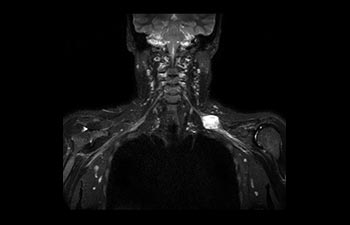

Enhanced diagnostic confidence in neuro oncology

Find the right clinical applications for your needs